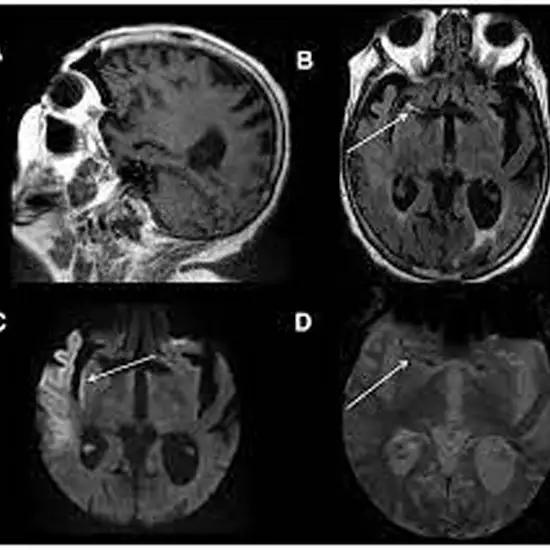

As per the profile of MRI Brain Stroke Protocol, you follow a group of MRI sequences which are put together in a specific way to better analyse brain ischemia.

This test basically focuses upon areas of brain injury, blockage of blood vessels and outline areas of critically decreased blood flow.

DWI The Diffusion weighted imaging (DWI) is the method of the signal contrast generation which is based on the differences in Brownian motion. Here, the DWI method would be used to evaluate your molecular function along with MRI Brain and the micro-architecture of the human body.

ADC Along with Diffusion MRI apparent and  diffusion coefficient (ADC) values along with normal brain and a classification of the  brain disorders based on the ADC values